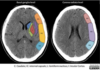

How well did you know this?

9

Foto ACM

ASPECTS

Puntaje 10 → TAC completamente normal en territorio de la ACM. Cada área con signos de isquemia resta 1 punto. 0 = infarto extenso. Profundas (3 puntos) N — Núcleo lenticular C — Cabeza del caudado IC — Cápsula interna Corteza (7 puntos) Dividida de anterior a posterior: M1 – Insular / opercular M2 – Corteza temporal anterosuperior M3 – Corteza frontal inferior M4 – Corteza frontal superior M5 – Corteza parietal superior M6 – Corteza parietal posterior

“3 Deep + 6 Cortical = 10”

🔹 Deep: Caudado, Lenticular, Cápsula interna 🔹 Cortical: M1–M6